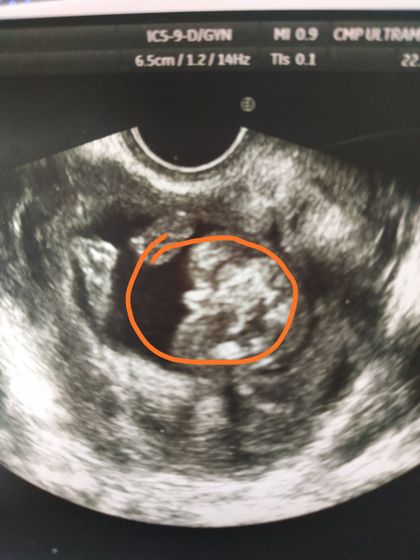

Доброго времени суток милые дамы ? Нужен взгляд уже бывалых и кто в этом разбирается. Сходила на УЗИ 16 недель, посмотреть пол. Ребенок не захотел поворачиваться нормально))) Врач сказала что 2/3 мальчик и 1/3 девочка ??♀️ Места себе не нахожу теперь. Не думала что мне прям невтерпеж знать кто в теремочке живёт)))) фото попы снизу, смотрели вагинально

Вот не особо понятно, если это в 16 недель узи, то скорее мальчик, у девочки уже не так торчит, если меньше срок то и девочка может быть

Я почему то сейчас думаю, что точно девчуля… Скокетничала. Мальчишки сразу не стесняясь все выдают ? В ближайшее время пойду снова смотреть, так как до скринига месяц, а я не вытерплю??

Мальчик) У девочек всё по-другому выглядит)

Непонятно у вас, вроде парень ) у меня мой парнишка вообще в 13.6 показал все добро, фото попы тоже снизу )